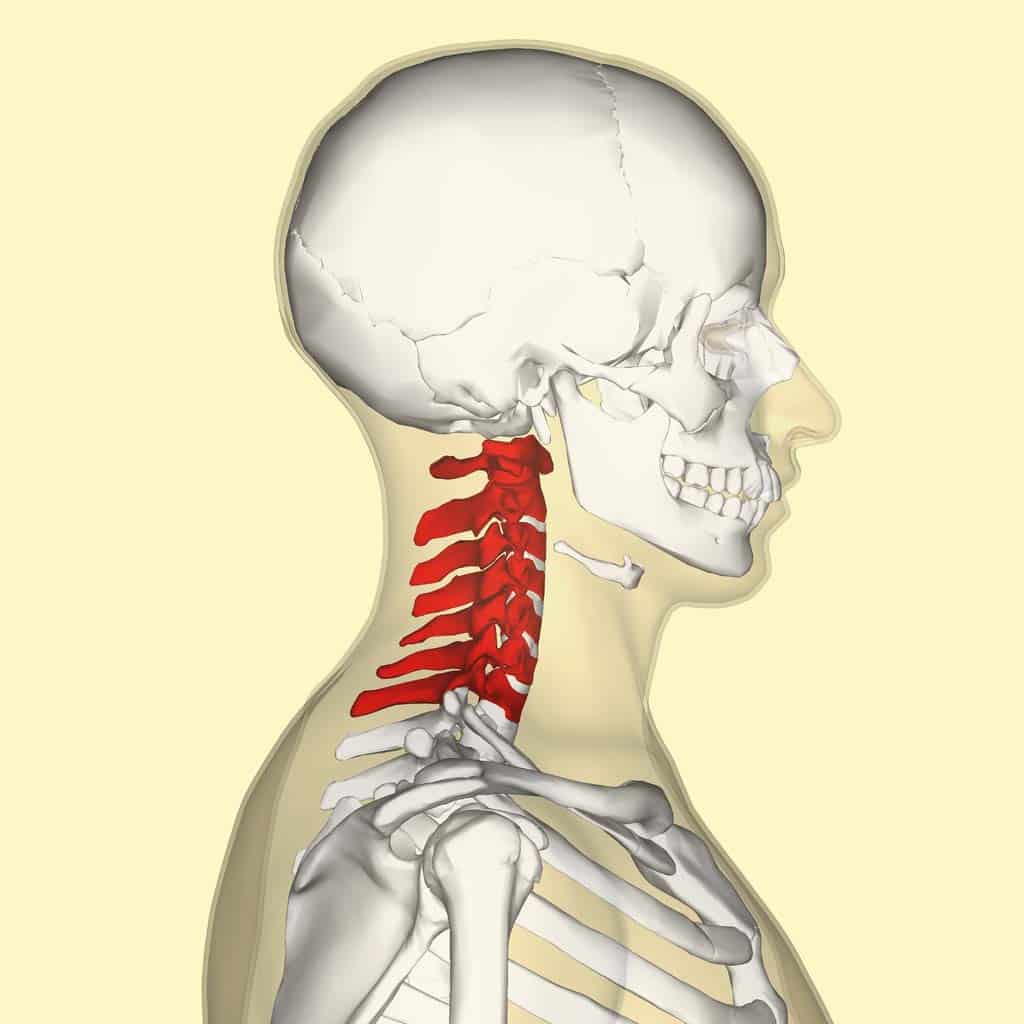

The Cervical Spine: Anatomy, Function, and Common | Spine Center of …

Normal Cervical Spine Anatomy – TrialExhibits Inc.

Anatomy of the Cervical Spine – TrialExhibits Inc.

The Cervical Spine – Features – Joints – Ligaments – TeachMeAnatomy